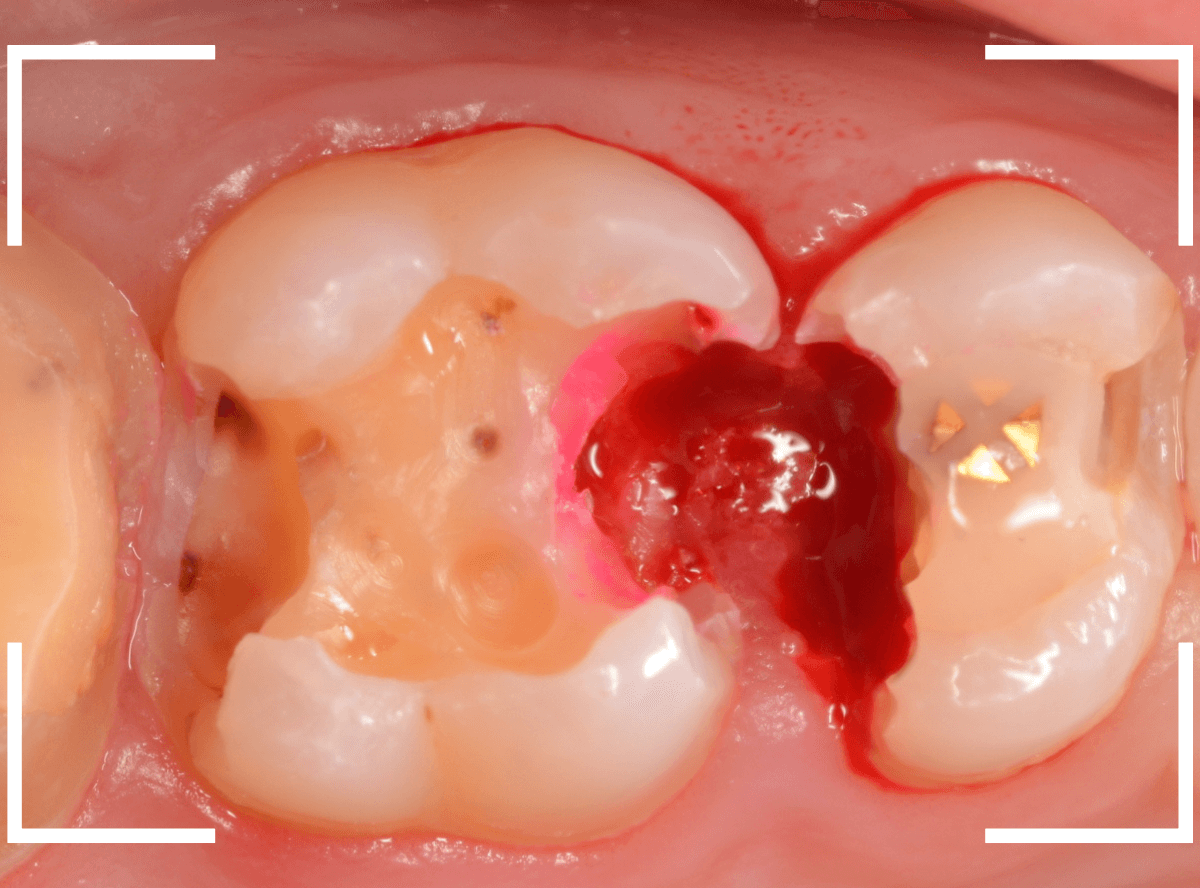

全ての虫歯を除去したところです。

抜歯した後ろのおやしらずは、元々虫歯の治療がしてありましたが、その際に抜歯しておいた方が良かったのではないかな、と思いました。